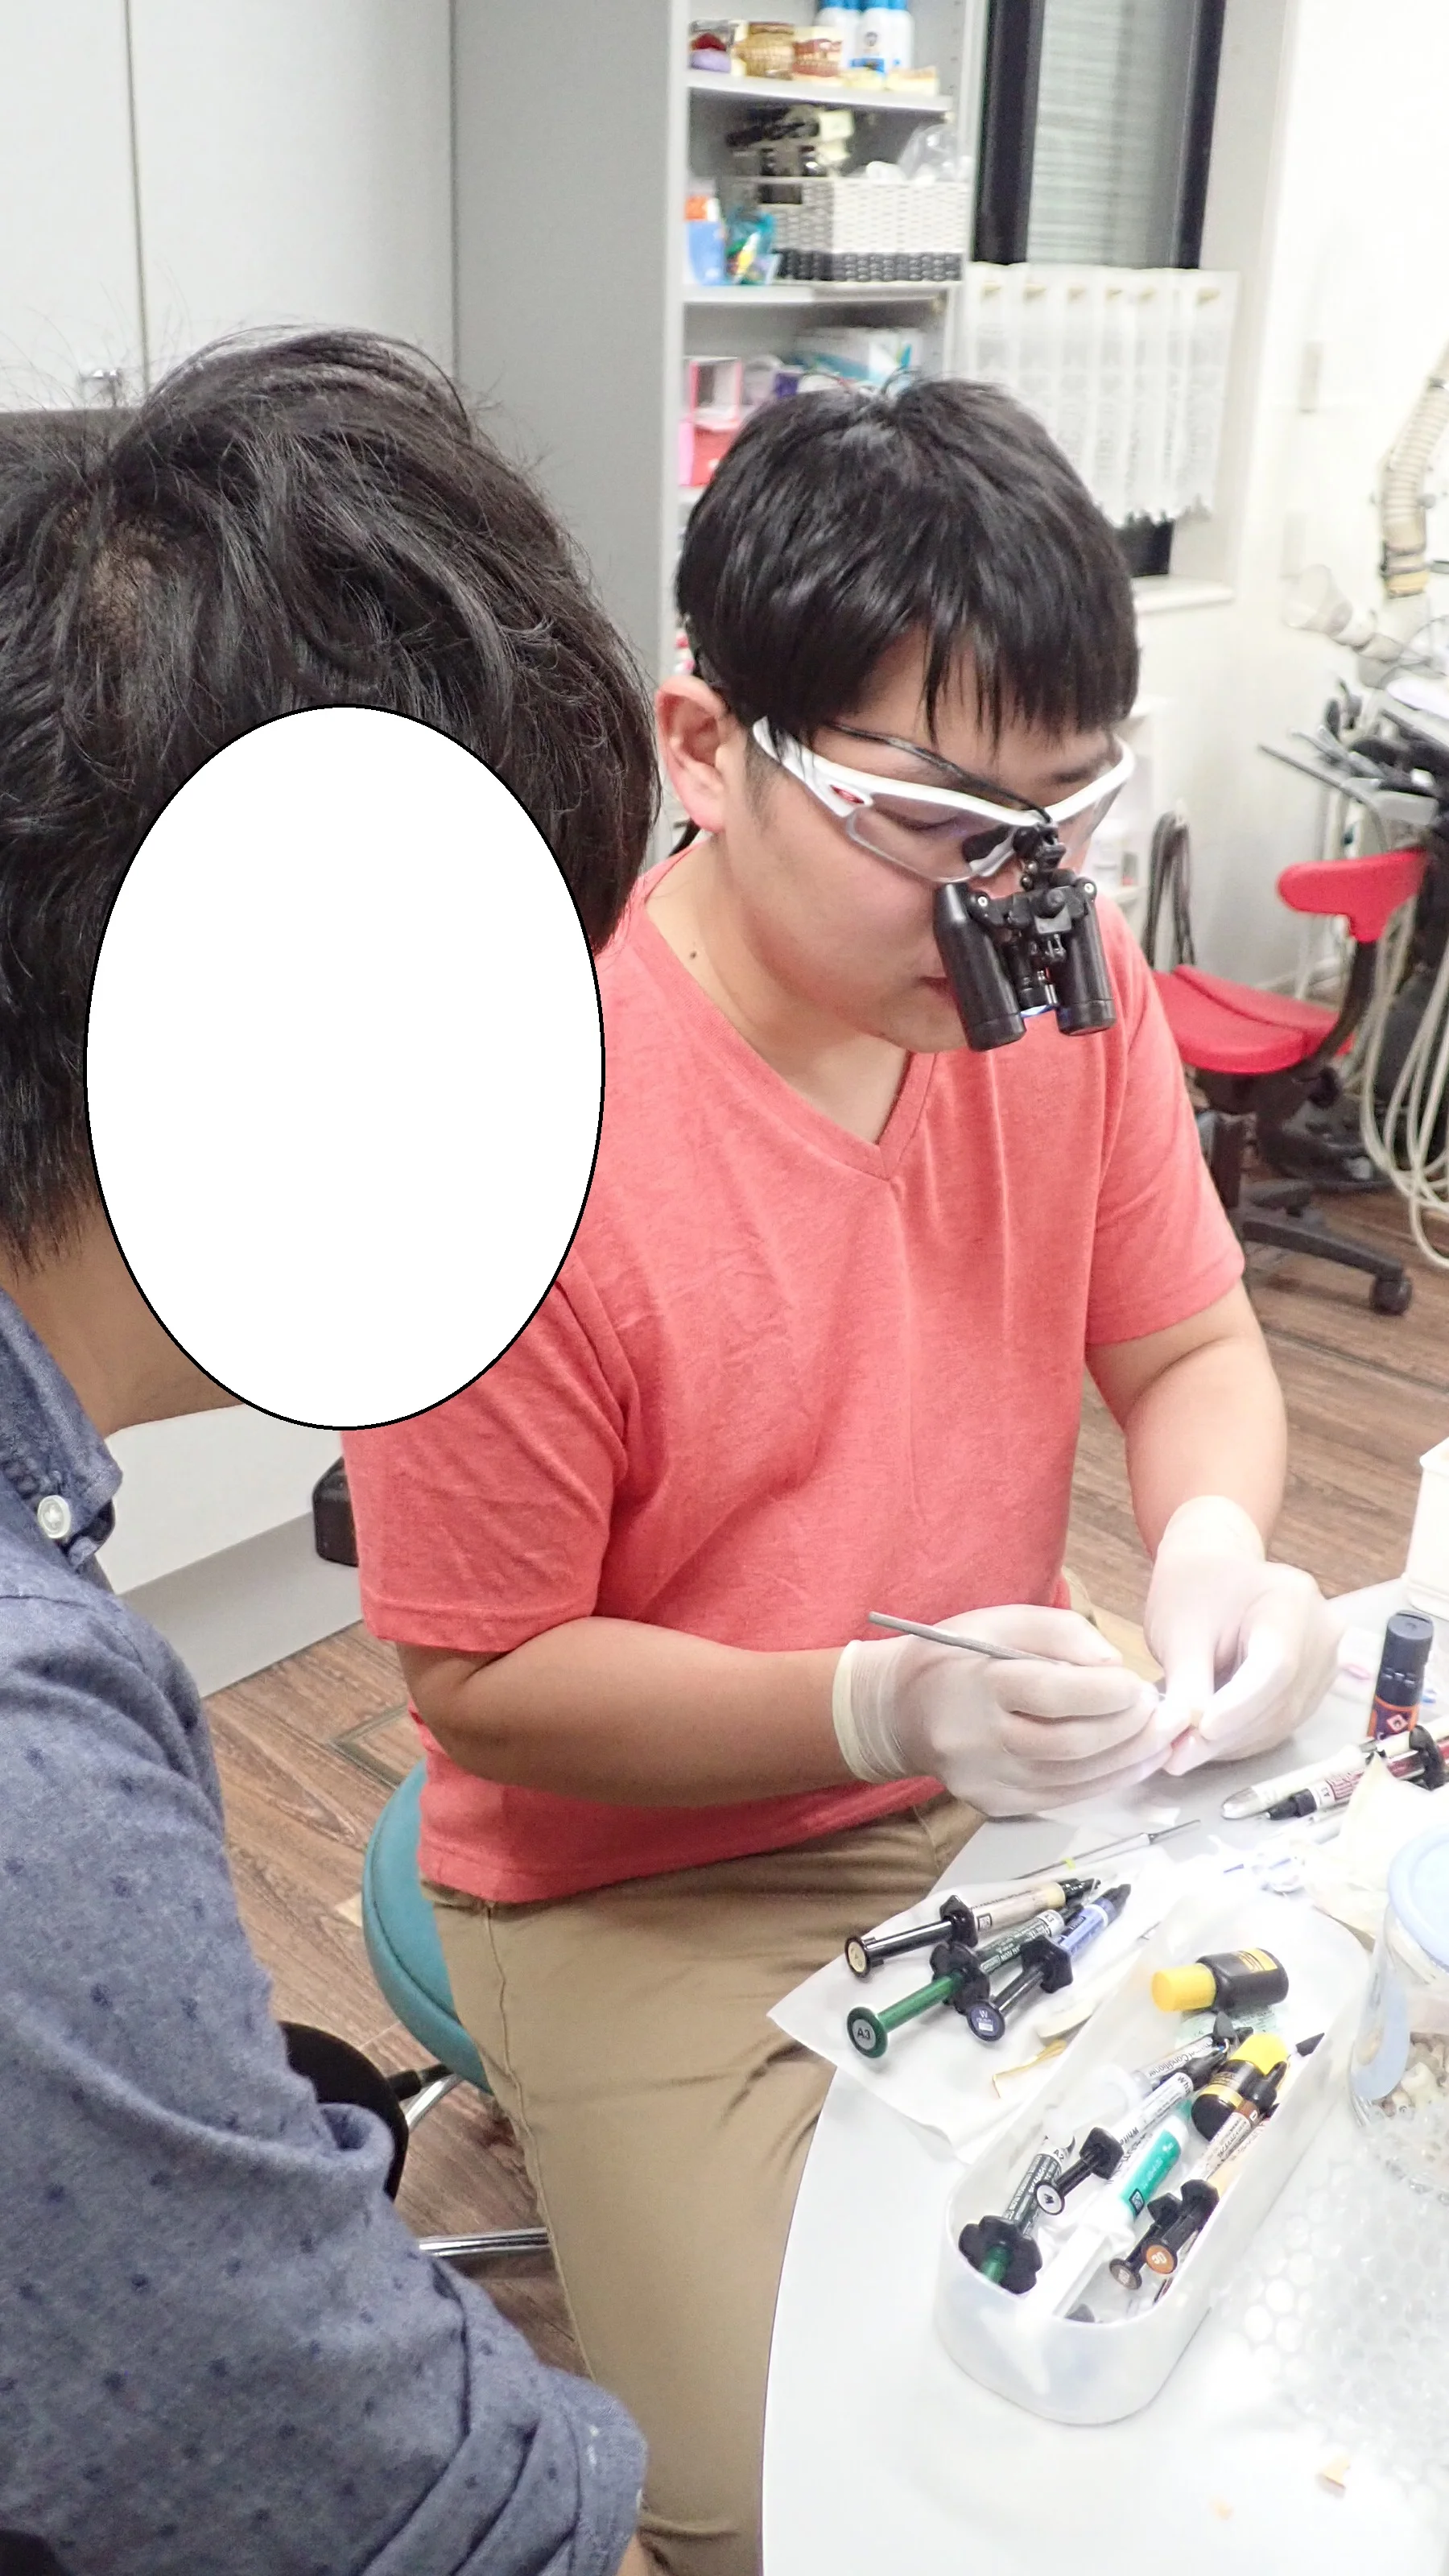

診療見学とハンズオンセミナーについて

こんにちは。 ここ最近歯科医師の方から「診療の見学」と「ハンズオンセミナー」のお問い合わせが非常に増えてきておりますので、そちらについて記載させていただきます。 【診療見学】 まず、診療の見学についてなのですが・・・ 当院は大学病院などの教…

続きを読む →